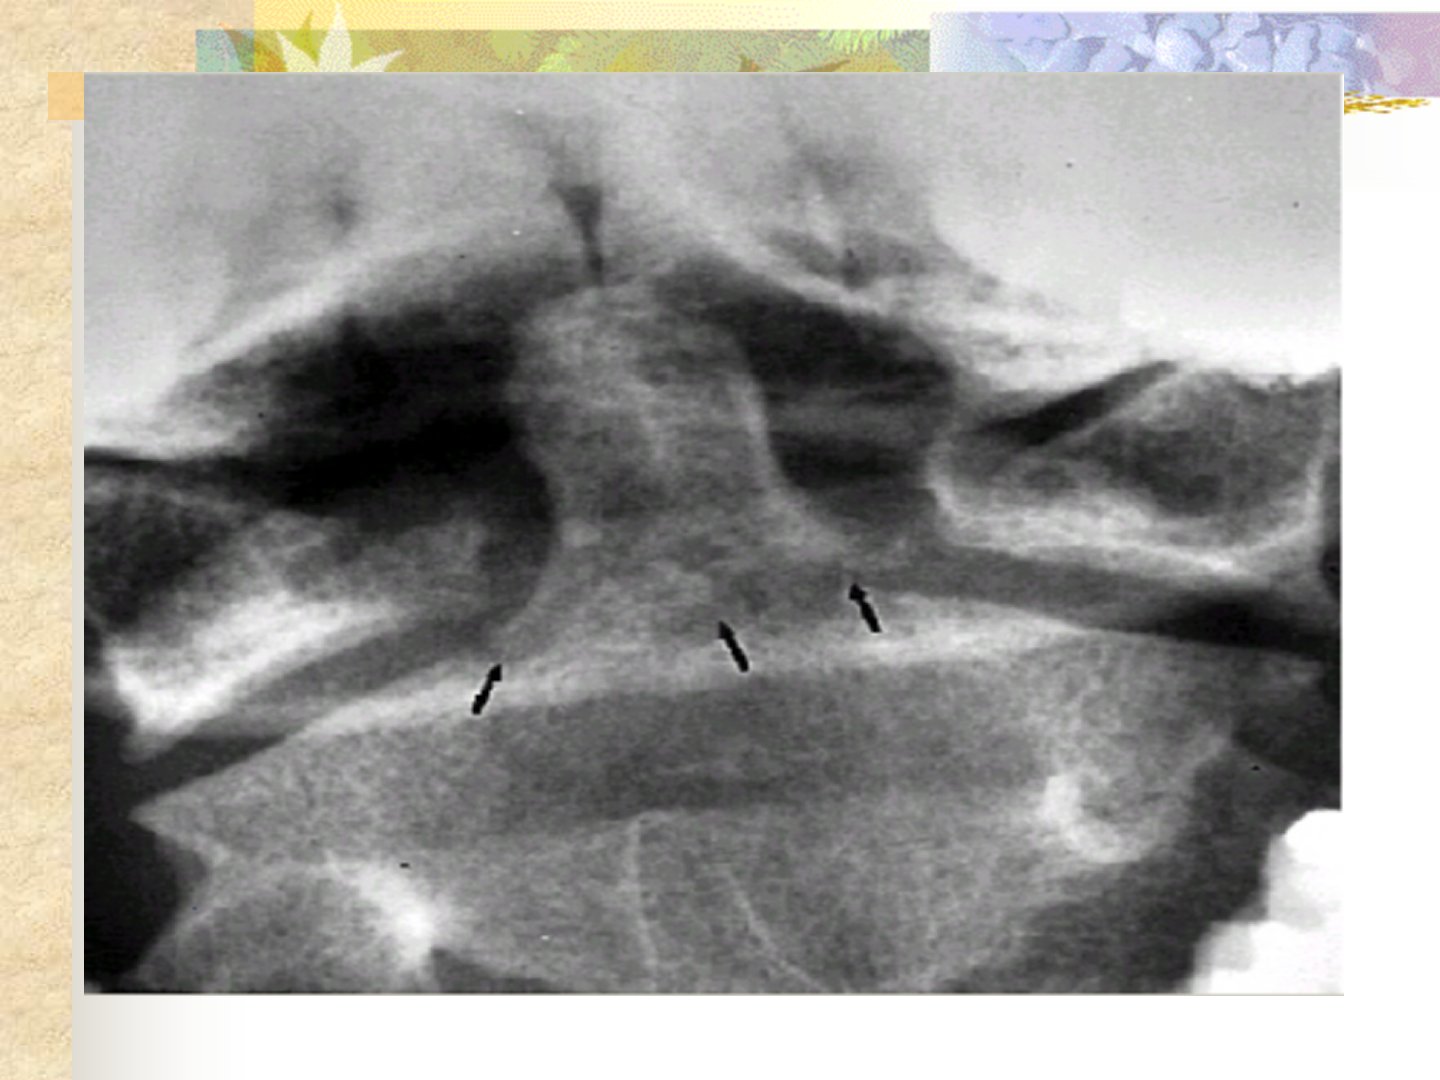

摘要:本文介绍了颈椎骨折与脊髓损伤的相关内容。颈椎骨折诊断方面包括外伤史、颈肩部疼痛及上下肢感觉运动障碍等症状通过体检和X线片、CT、MRI等辅助检查确诊。治疗上颈椎半脱位采用石膏颈围固定或脊柱融合;稳定型颈椎骨折轻度用枕颌带牵引固定严重则用颅骨牵引固定合并脊髓损伤需手术;单侧小关节脱位行颅骨牵引融合;爆破型骨折手术治疗;过伸性损伤用颅骨牵引固定;齿状突骨折视类型保守治疗或手术。脊髓损伤分为脊髓震荡、挫伤与出血、断裂、受压及马尾神经损伤等类型临床表现多样并发症包括呼吸衰竭等。治疗上保守治疗有牵引、脱水等手术治疗则针对有脊髓受压表现者尽早手术减压。